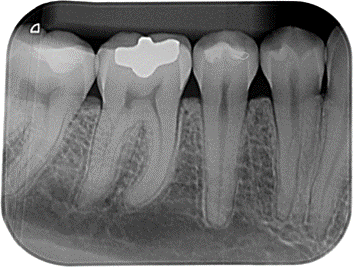

PERIAPICAL